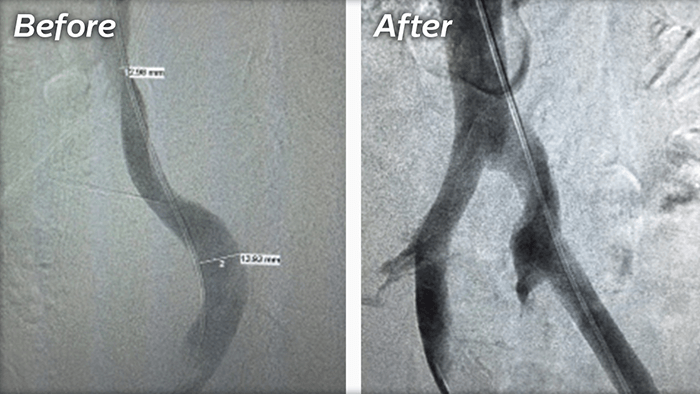

SVI Treatments

There are multiple ways to manage SVI, depending on the extent of the diseased veins. For some people, changes like adopting a healthy diet and increasing exercise can help reduce the pressure around the legs thereby reducing the progression of varicose veins.

Seeking treatment can be strictly cosmetic while other people will wait until they have pain or ulcers. If you are experiencing symptoms that bother you discuss this with your doctor, because they can potentially lead to leg ulcers.

After consulting your doctor, he may recommend the following treatments:

Ablation Therapy

A minimally invasive treatment that uses lasers, radiofrequency, non-thermal ablation or mechanochemical ablation to shut down large varicose veins in the legs.